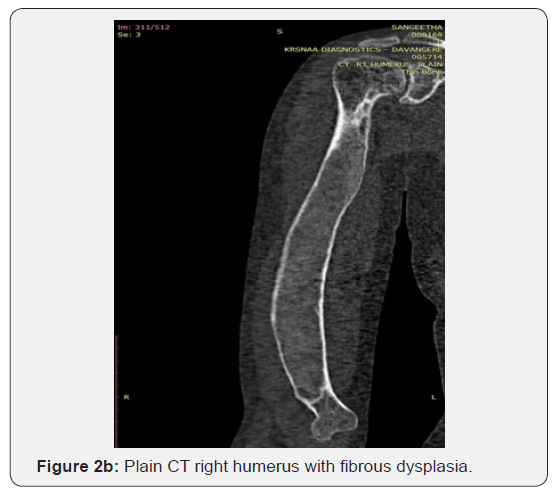

j) CT scan of right arm and forearm shows polyostotic pattern of fibrous dysplasia of right humerus and radius with ulnar sparing (Figures 2a-2d)

Our patient has presented with pain and deformity over right arm and forearm from past 5 years. She was further evaluated which shows the elevation of serum alkaline phosphatase and decreased serum vitamin D3 levels. Radiograph of right arm and forearm shows the classical features of polyostotic fibrous dysplasia with ulnar sparing and without any pathological fractures. CT scan of right arm and forearm outlined the delineation between normal and diseased process of the bony architecture. The patient was offered for open biopsy of right distal humerus with GA. Then the histopathological report showed trabeculae of woven bone which lacks osteoblastic rimming in a Chinese letter pattern surrounded by fibroblastic proliferation admixed with few osteoclast-like giant cells which confirmed the diagnosis of polyostotic fibrous dysplasia of humerus and radius with ulnar sparing (Table 1).